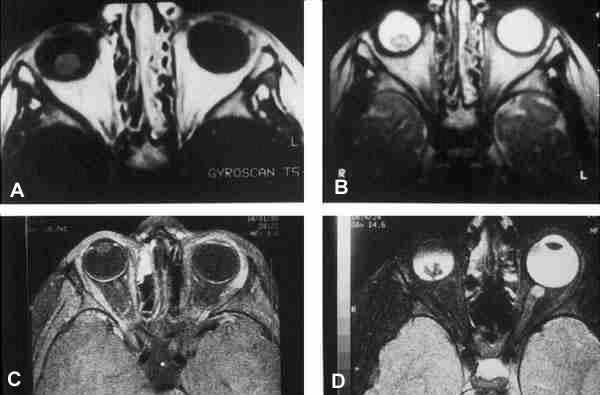

25-04.jpg (36066 bytes)

Figuras 4a, b, c y d. Retinoblastoma en ojo derecho.

Secuencias potenciadas en T1 tras la administración de gadolínio (a) y potenciada en T2 (b). RM de control 17 meses tras finalizar el tratamiento (c, d).

Ausencia de captación tumoral de gadolínio (c) así como reducción del componente cálcico (d) respecto a estudio basal potenciado en T2 (b).